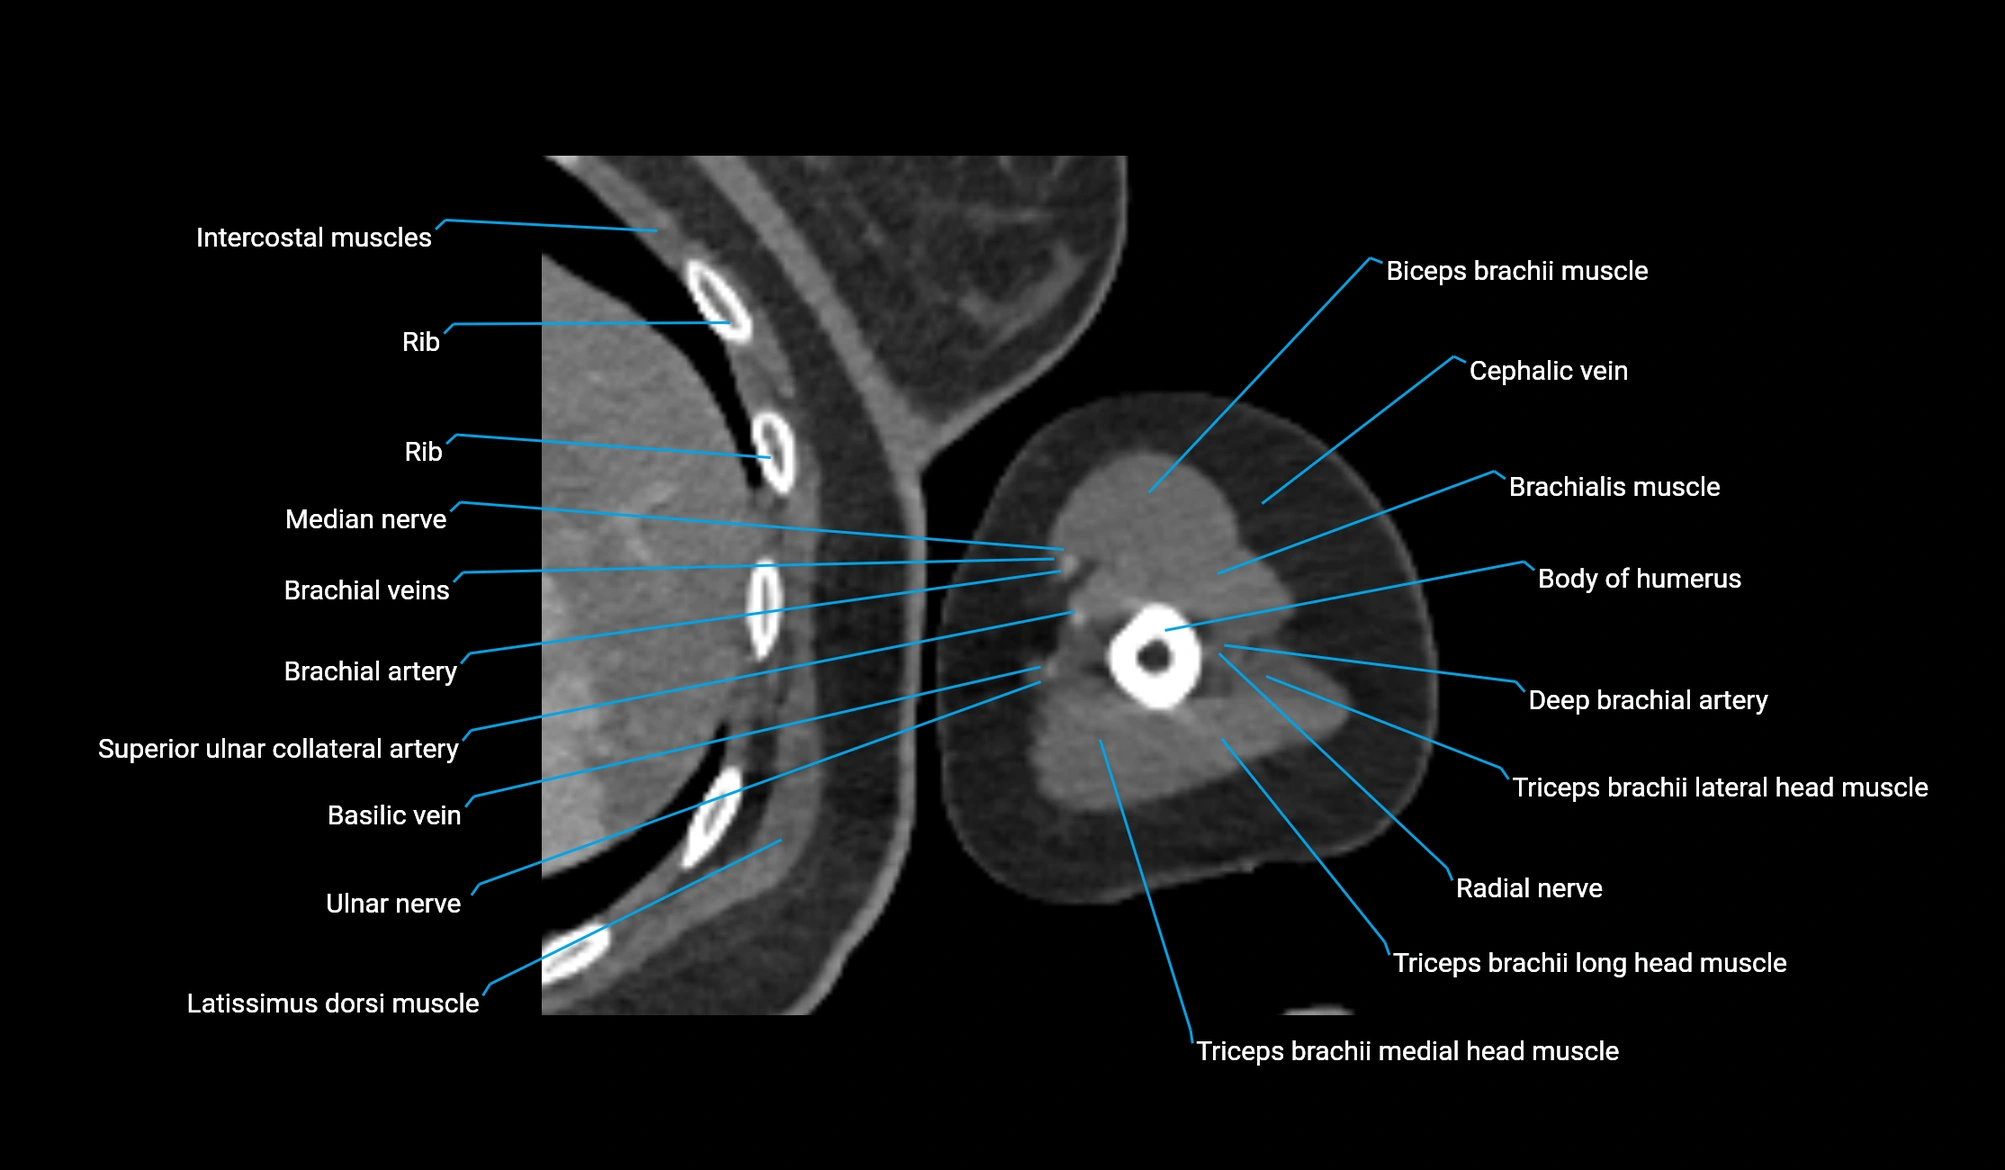

- Body of humerus

- Brachial artery

- Brachialis muscle

- Brachioradialis muscle

- Cephalic vein

- Deep brachial artery

- Lateral head of triceps brachii muscle

- Long head of triceps brachii muscle

- Medial head of triceps brachii muscle

- Median nerve

- Radial nerve

- Superior ulnar collateral artery

- Triceps brachii muscle